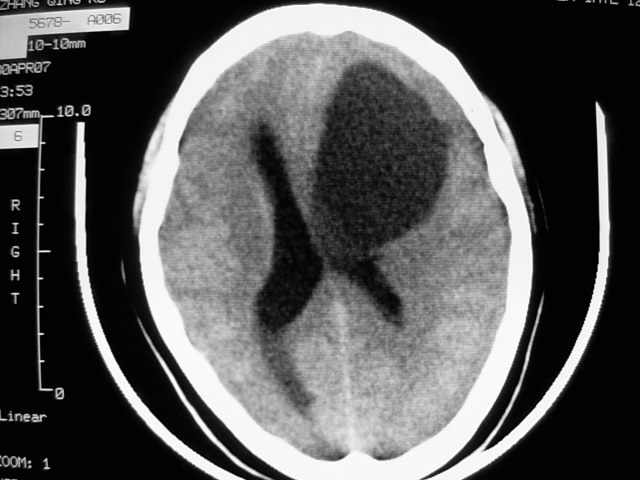

f39y,头疼、眩晕。患者拒绝强化。

左侧脑室增大,前角明显,中线向右移位,左侧脑室内见一肿块,密度不均,1室管膜瘤?2脑囊虫?

左额叶见一巨大椭圆形略低、低密度混杂密度肿块,边界清楚,似与侧脑室额角相通,明显占位效应,左侧侧脑室受压变形,右侧侧脑室扩大,中线结构向右明显弧形移位。鞍上池闭塞。

考虑:1、左额叶良性占位性病变,以皮样囊肿可能性大,伴镰下疝。

左侧脑室增大,前角明显,中线向右移位,左侧脑室内见一肿块,密度不均,内见钙化,1室管膜瘤?2脑囊虫?

类圆形低密度病灶与脑室内密度明显有差别,考虑:低密度病灶压迫四脑室形成的特殊影像。支持:皮样囊肿。

感觉病灶位于侧脑室前角内,而体部受压,病灶形态同前角一致,右侧脑室前角变形并不太严重,病灶呈混杂密度,考虑皮样囊肿或室管膜瘤可能性大一些。